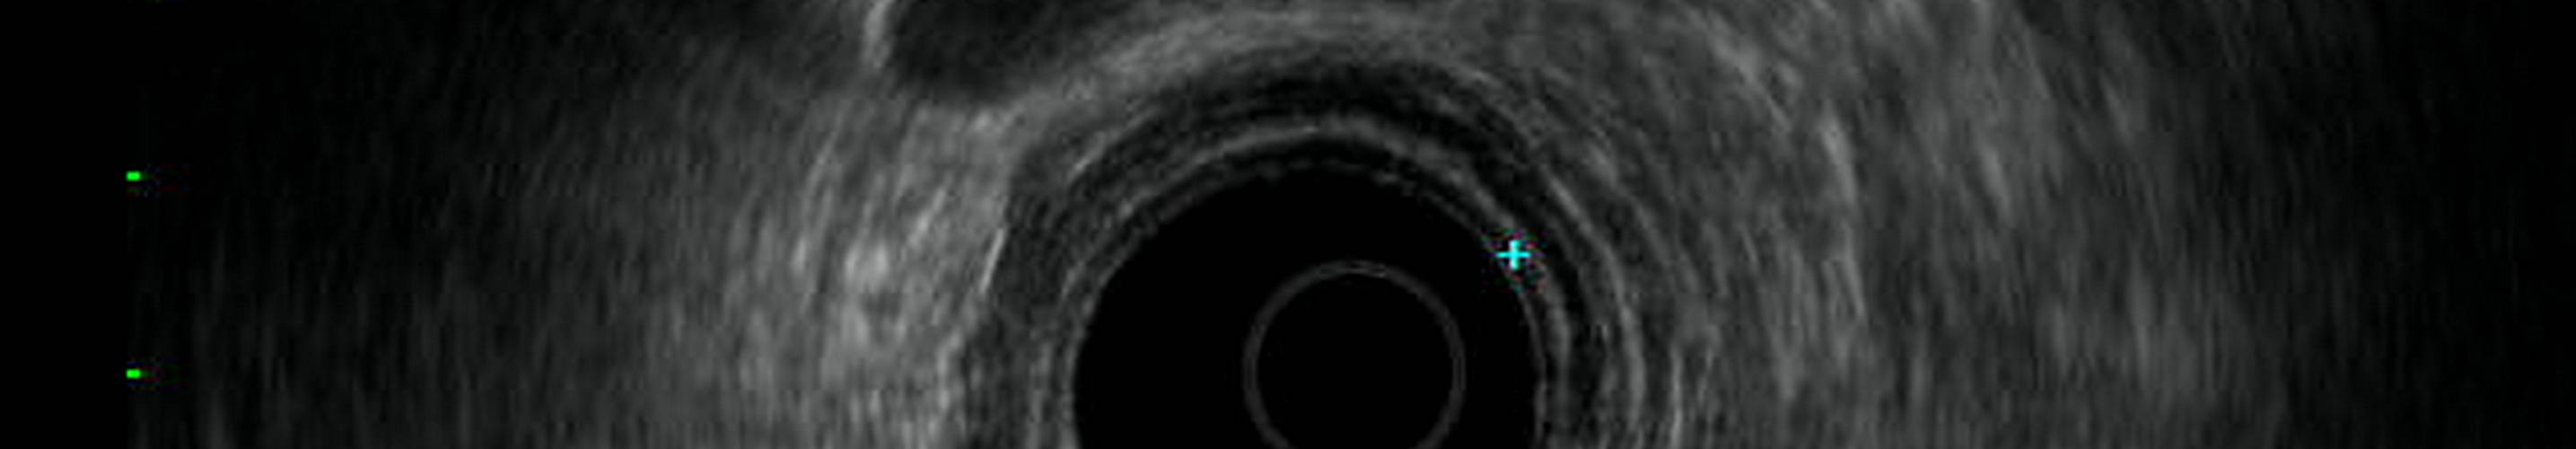

Endoskopie, Vorsorge-Coloskopie, Proktoskopie, Sonographie und